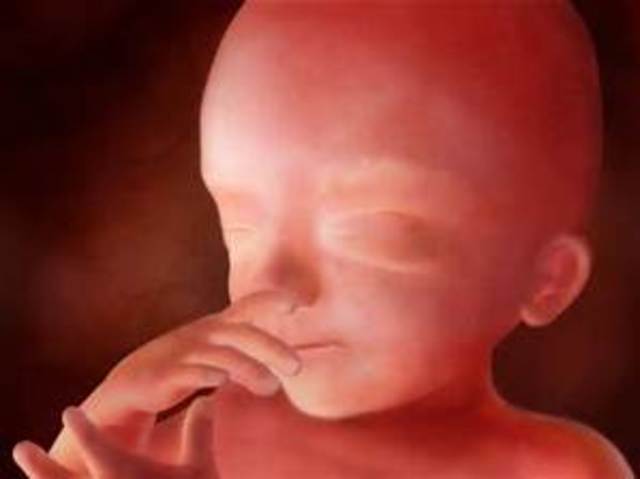

• Week 11

Week 11

By week eleven, the baby has begun developing ears, toes, an upper lip, and twenty teeth. Also during this week the genitals of the baby have begun to develop.

• Week 12

Week 12

By week twelve,the baby's facial profile, brain, and vocal cords are fully developed. Also by this week you'll be able to hear your baby's heartbeat.